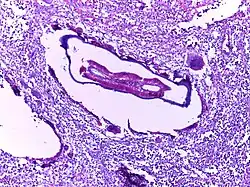

![]() |

Filarial lymphadenitis | Micrograph showing section of an adult filarial worm. Surrounding tissue shows dense infiltration of eosinophils. | Category: Histopathology of filariases | filariasis |